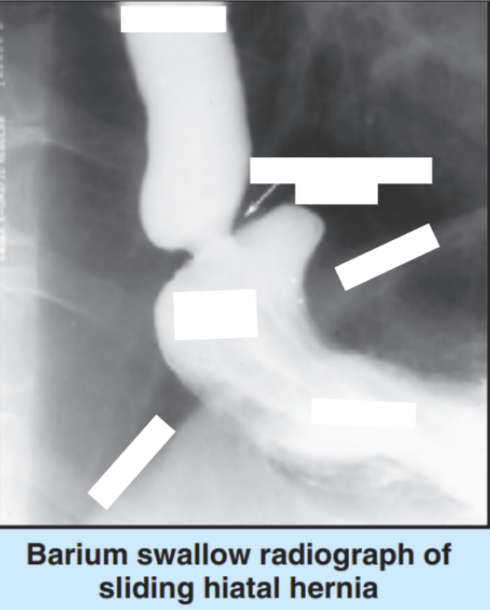

This is a double contrast examination. What is it showing?

A peptic ulcer that is on the posterior wall of the antrum

What does this image show?

Giant gastric ulcer that is located more proximally in the stomach